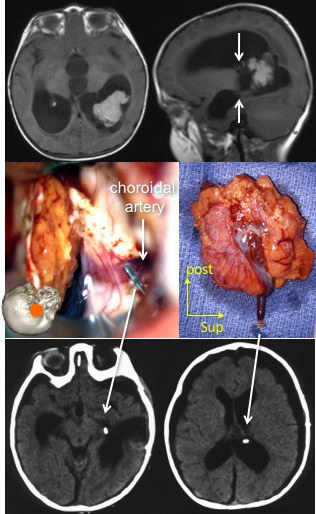

- la voie trans-temporale : elle permet le contrôle premier de l’artère choroïdienne antérieure (typiquement pour les papillomes du plexus (cf. ci-dessous)

il se pose de façon différente selon le type de tumeur : dans le papillome (ci-contre), le contrôle premier de l’artère choroïdienne antérieure, puis de la veine thalamo-striée, enfin l’exérèse en bloc permet une chirurgie pratiquement exsangue.

à l’inverse, le carcinome du plexus recrute des pédicules venant de toute la surface du ventricule et le saignement se poursuit jusqu’à la fin de la résection. Il faut surtout être prudent vers la ligne médiane car un saignement du système veineux cérébral interne et de la veine de Galien pourrait être fatal.